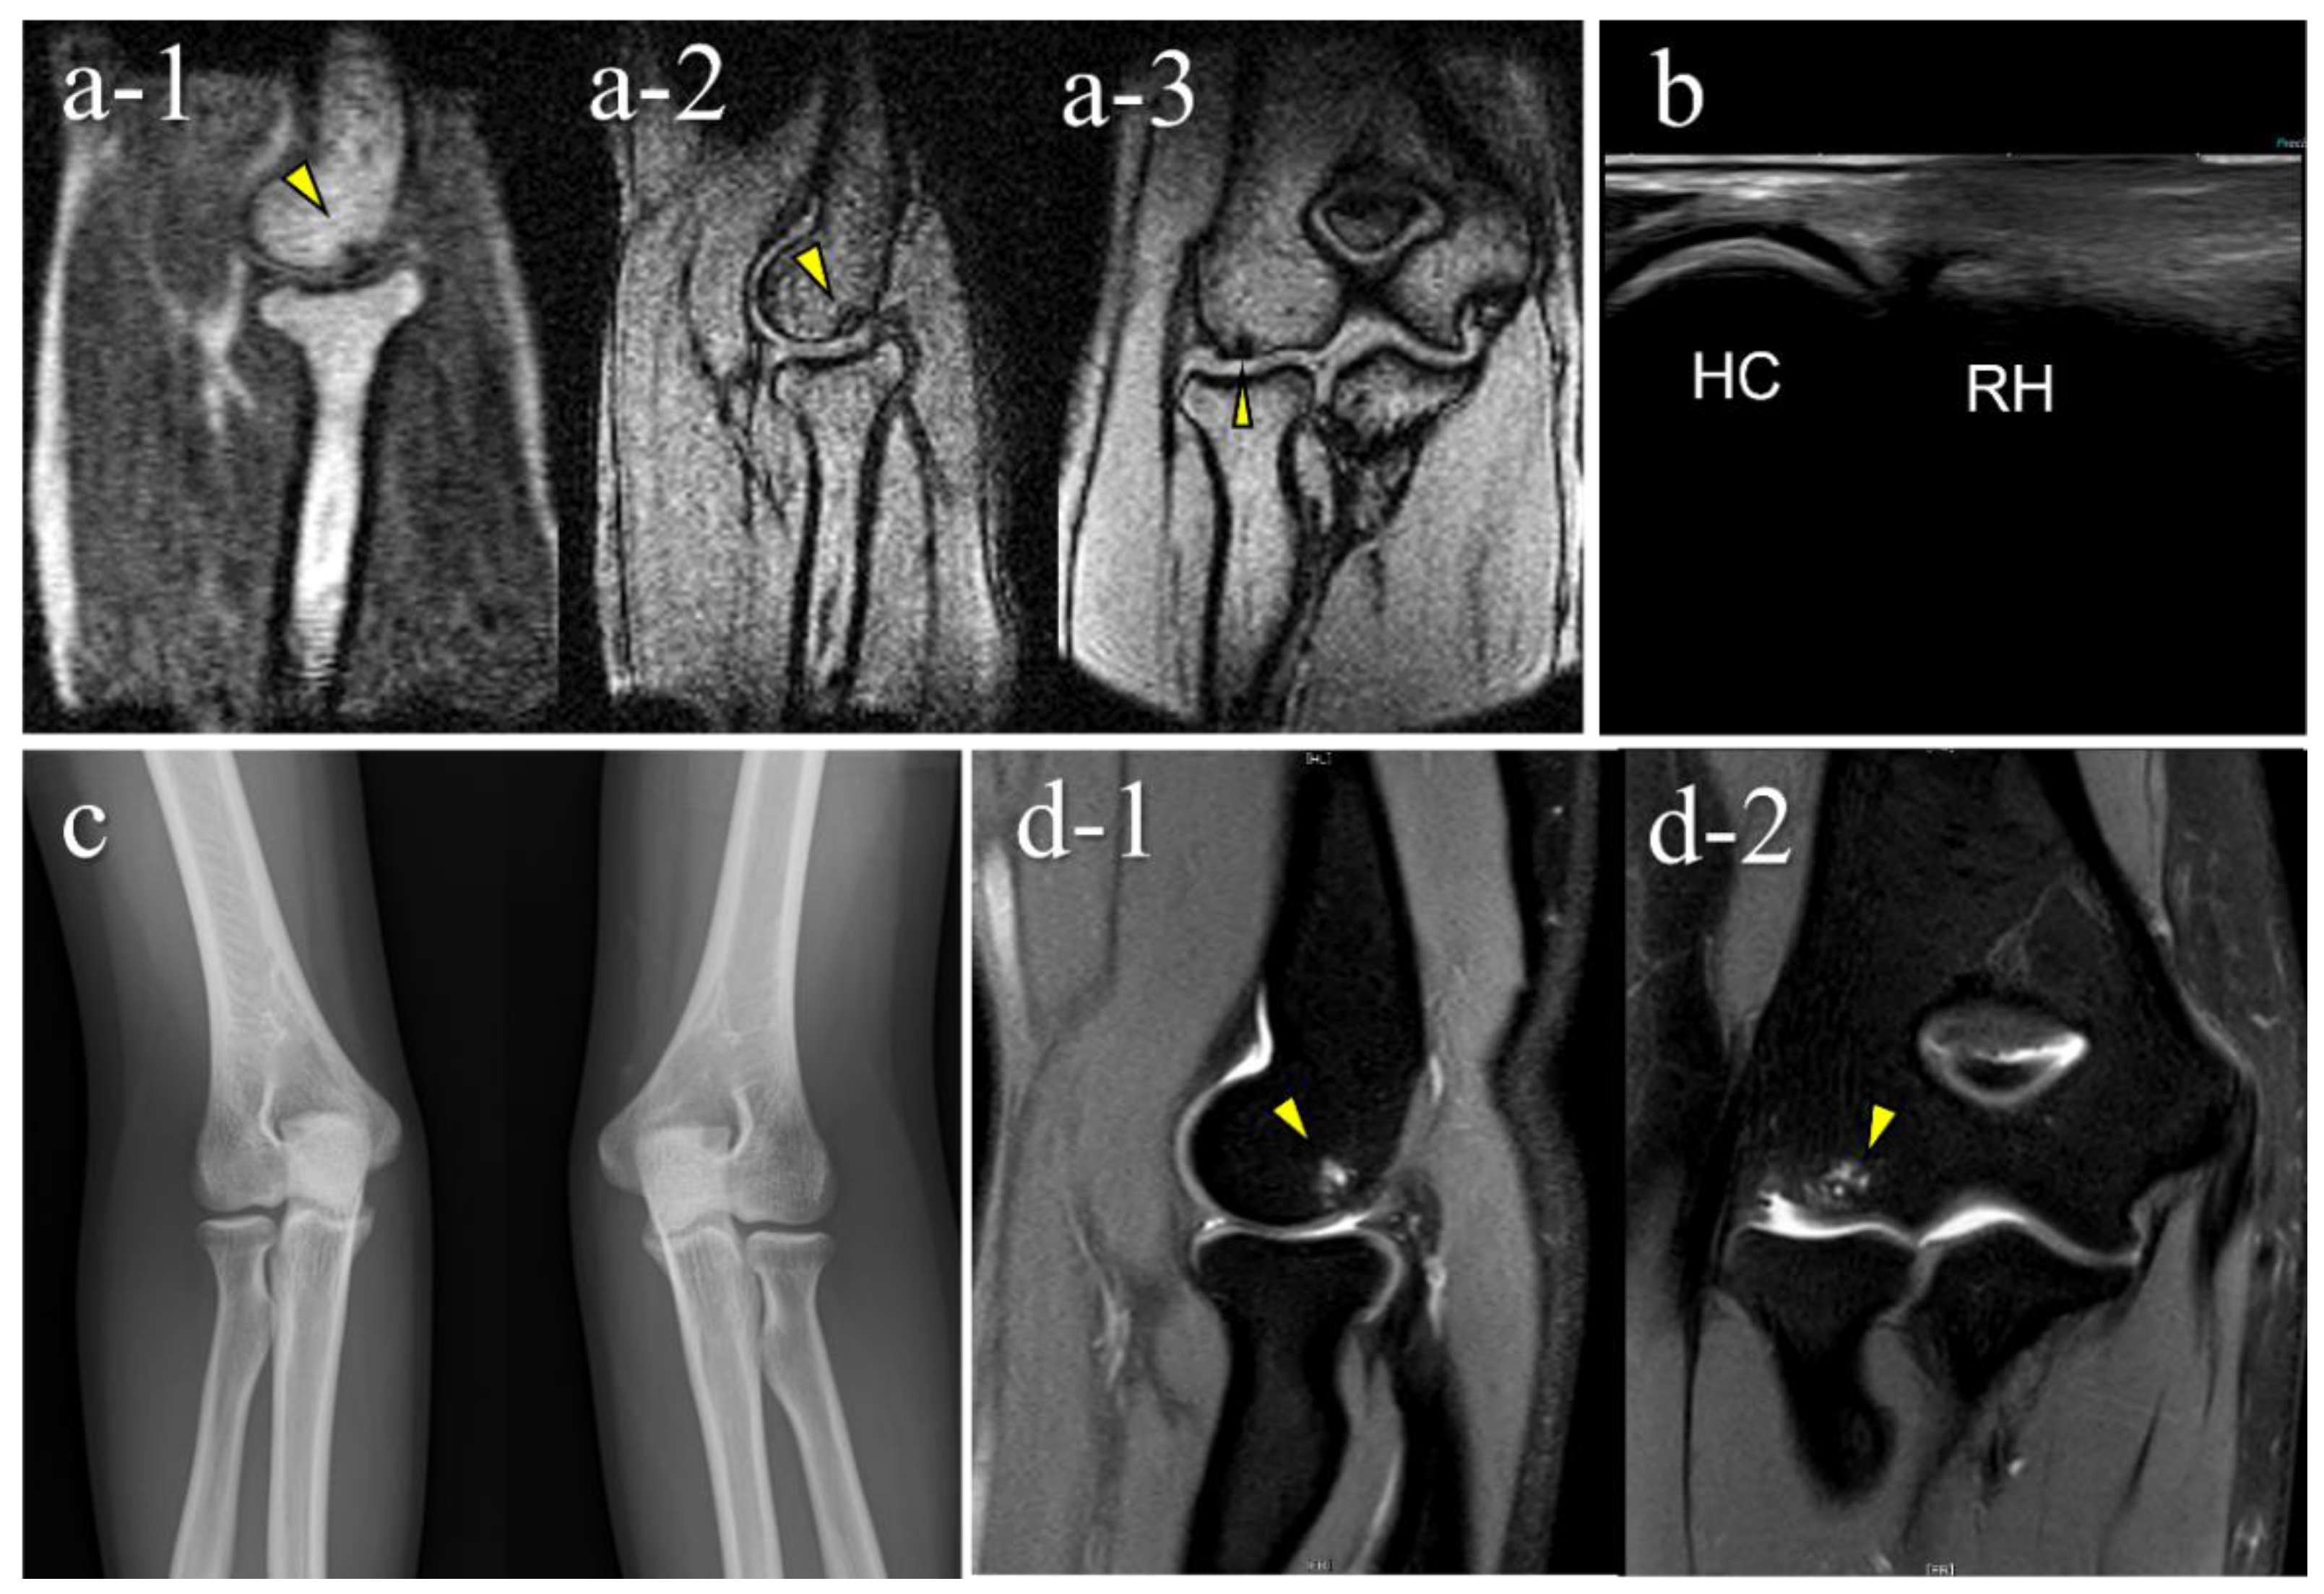

| 4 | 12 | M | + | + (2nd) | + (B) | OCD | II | lateral | 11 |

| 5 | 12 | M | + | + (2nd) | − (B) | OCD | I | central | 3.5 |

| 6 | 15 | F | - | + (2nd) | − (C) | not OCD | posterior | 3.5 | |

| 7 | 12 | M | - | + (2nd) | − (D) | OCD | I | central | 5.5 |